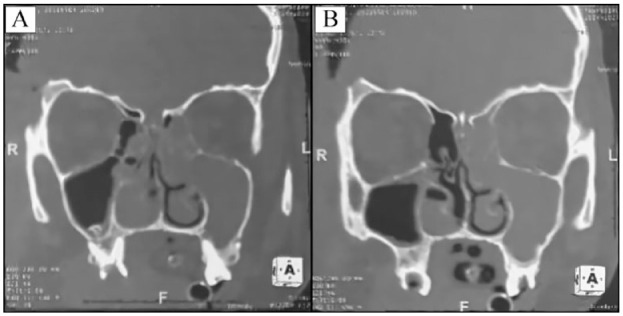

Case reports: A 22-year-old female and 30-year-old male patients, both with no significant medical history, presented with subdural empyema and intracranial epidural abscess, respectively, both complicating pan-sinusitis of dental origin. Successful outcomes were achieved with surgical drainage of the lesions, antibiotic therapy, and extraction of affected teeth. Female patient underwent further management for neurological sequelae, while male patient was discharged without neurological complications.

Abstract Image